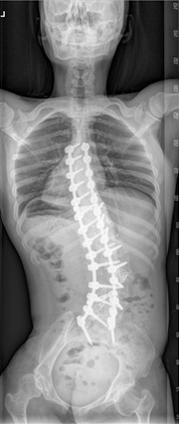

신경근육성척추측만증

수술 전 전신 x-ray 사진

수술 후 전신 x-ray 사진